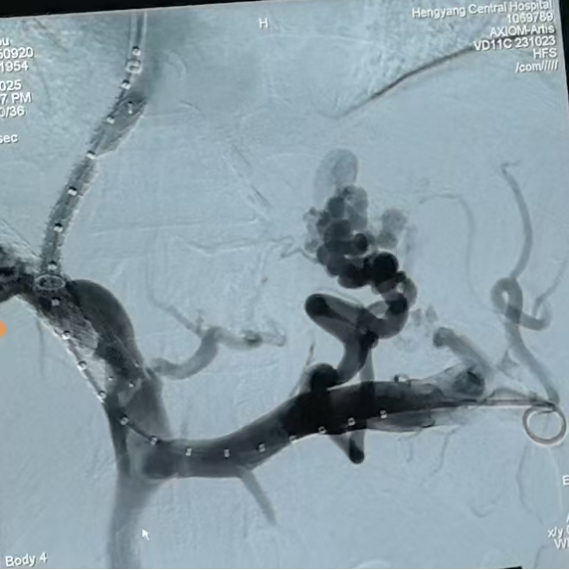

第三步,手術(shù)實施與術(shù)后管理。9月20日,在消化介入團隊精湛操作下,成功為患者實施TIPS支架修補術(shù)。術(shù)中,團隊克服了患者肝內(nèi)血管結(jié)構(gòu)因既往手術(shù)和肝硬化而異常復(fù)雜等諸多困難,精準(zhǔn)地在門靜脈與肝靜脈之間建立了有效分流,并置入覆膜支架以確保分流道長期通暢。術(shù)后門靜脈壓力即刻顯著下降,達到了預(yù)期血流動力學(xué)目標(biāo)。

wps10.png

圖二:TIPS術(shù)中影像